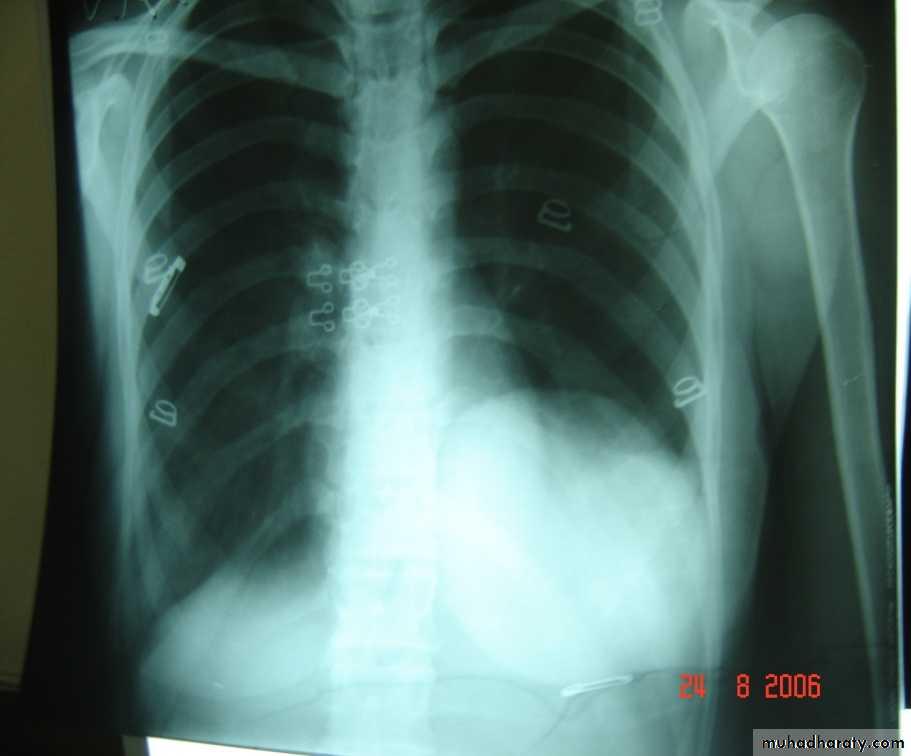

• Chest X-Ray

• Can shows the characteristic air fluid level ,may associated with pleural thickening , pneumothorax

• CT chest is helpful in demonstrating the abscess .